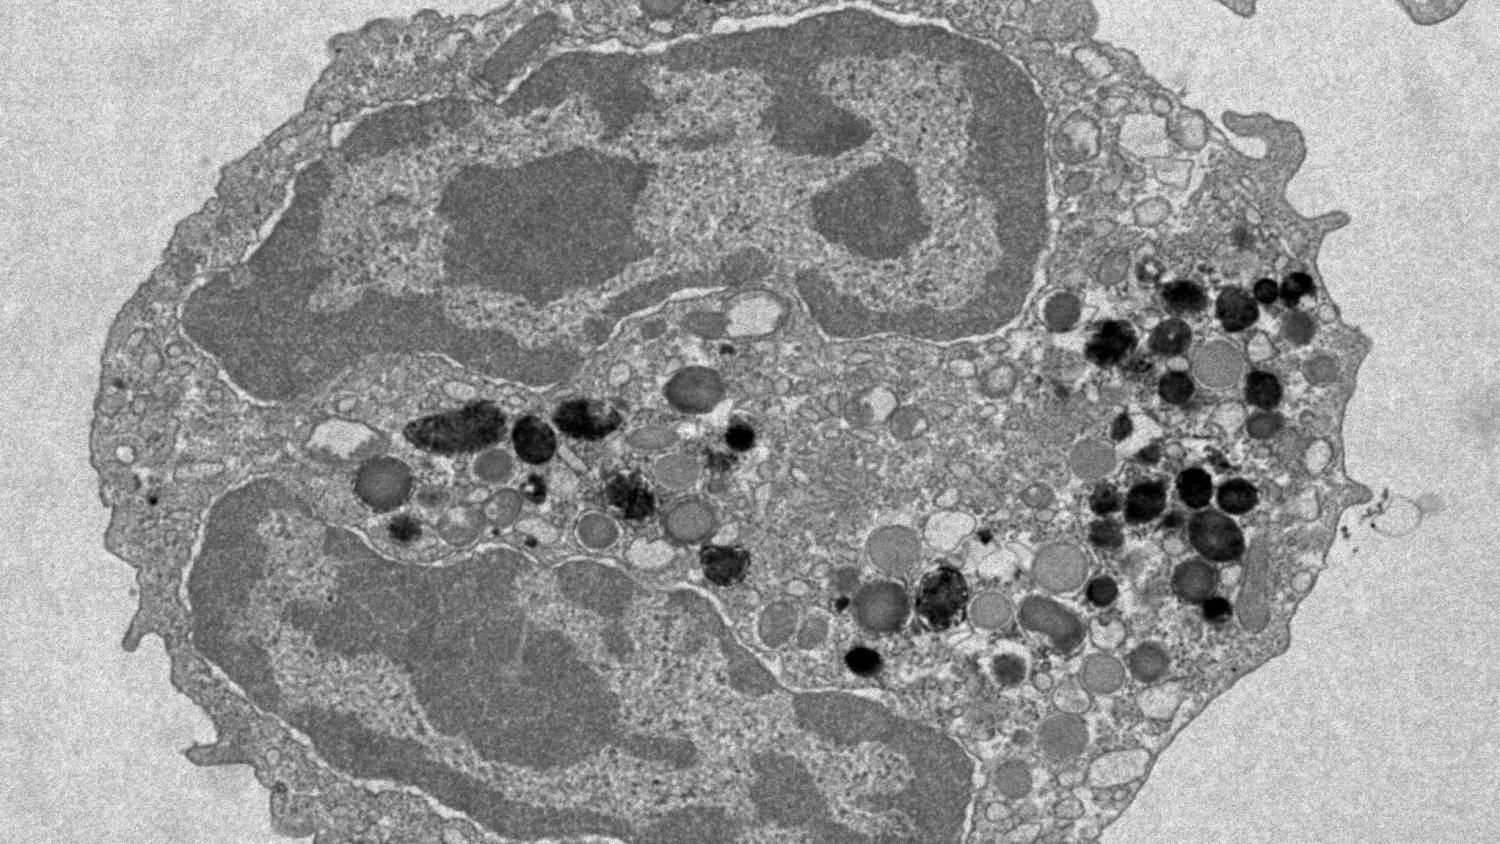

Analyzing blood from over 200 men in each category, the scientists zoomed in on hematopoietic stem cells (HSCs), aka blood stem cells. These cells naturally mutate as we age, which leads to clones with subtly different genetic makeup, a process known as clonal hematopoiesis. While this is normal, certain mutations can cause blood cancers.

Giving blood didn’t affect the cells’ likelihood of undergoing clonal hematopoiesis — it was found to be just as common in frequent donors versus sporadic. However, the researchers noticed that the genetic makeup of blood cells in each group varied when it came to a gene called DNMT3A, which is known to mutate in people who develop leukemia.